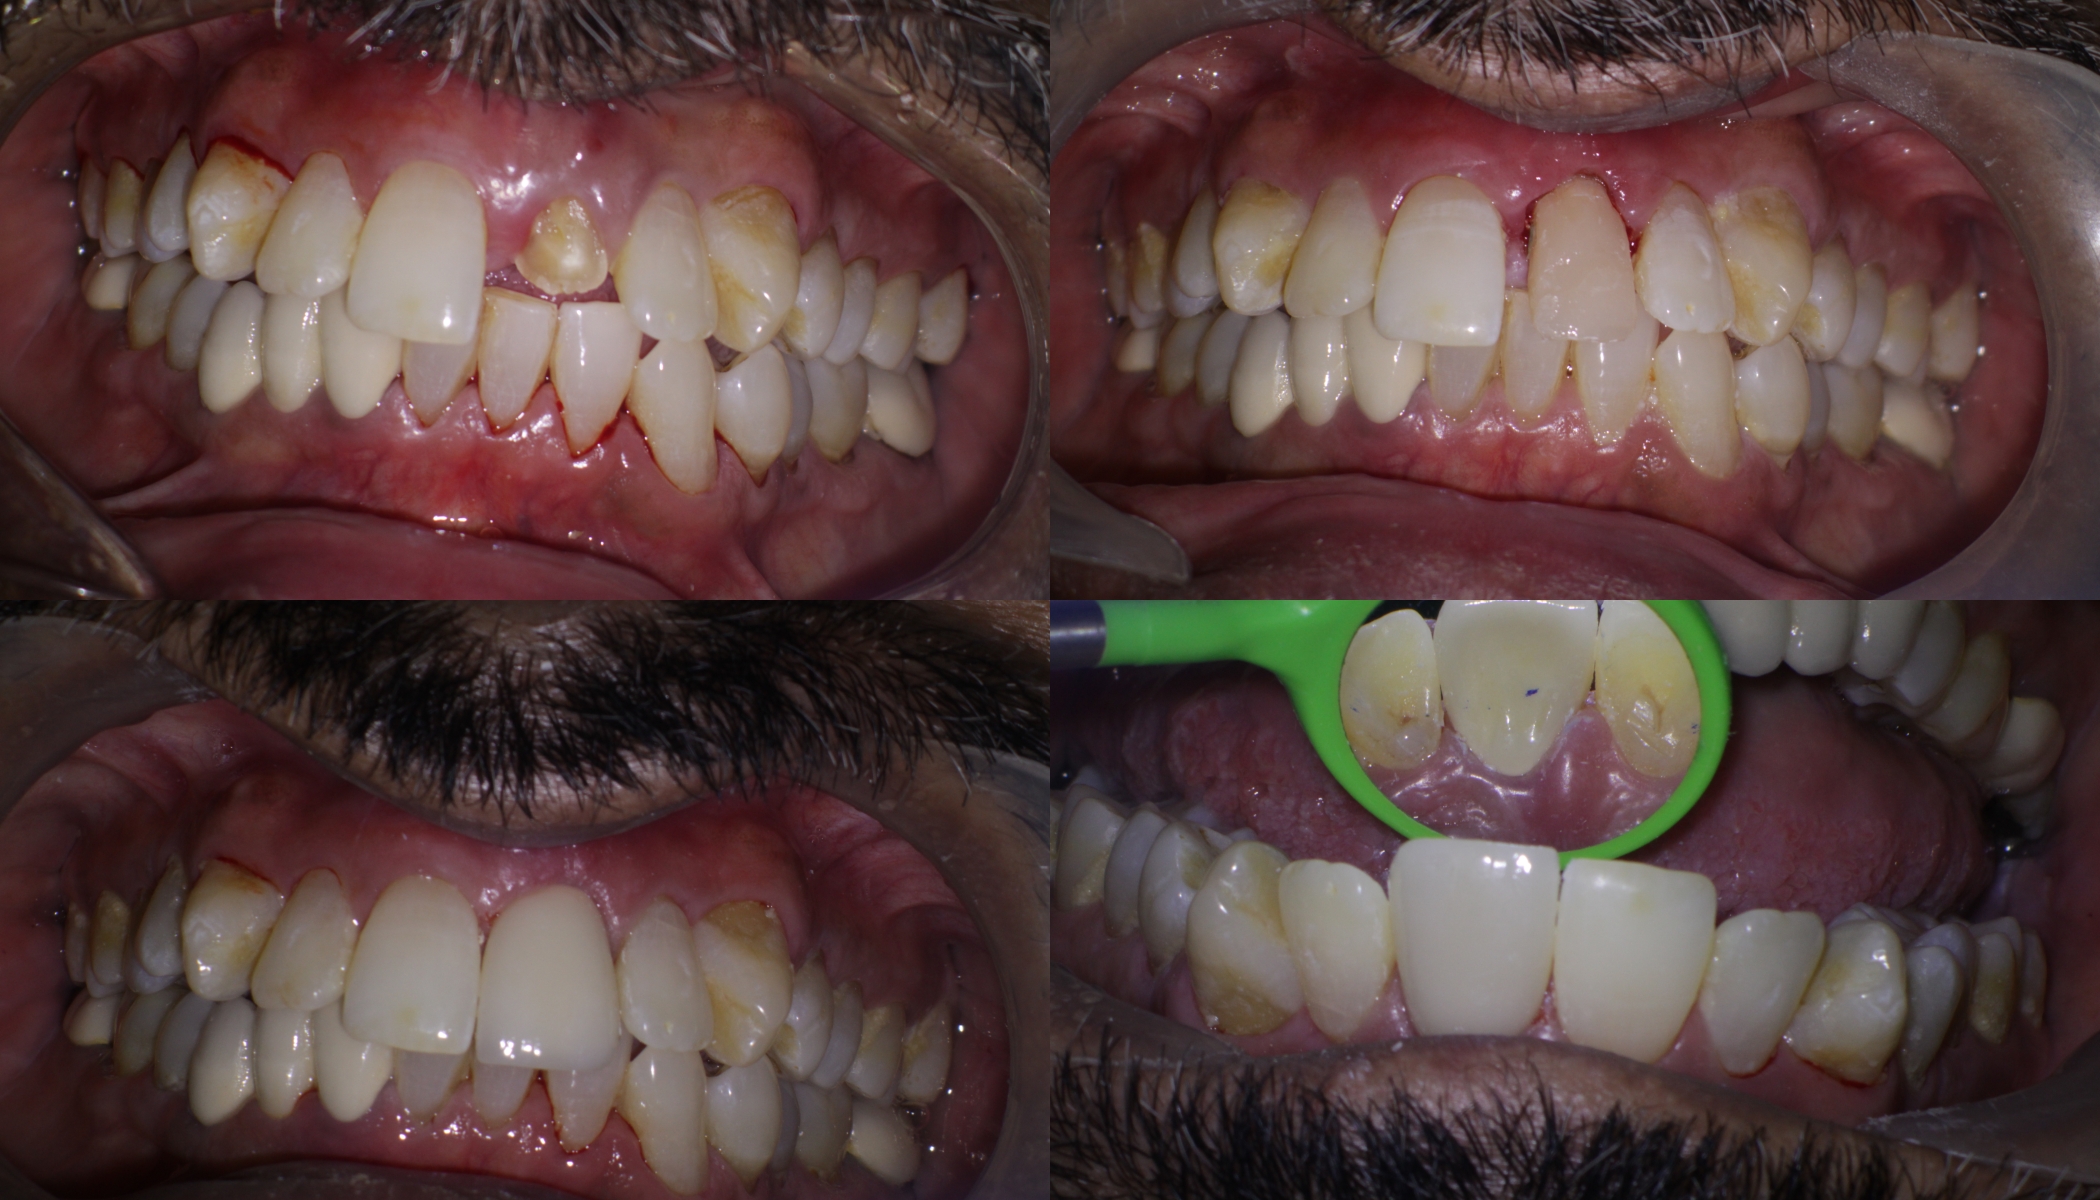

Pt 55 yoM presented with fracture of #9. History of trauma 2 wks back and was aymptomatic. Gingivectomy using electrocautery was done. Root canal therapy was completed after intermittent CAOH dressing , fibre post cemented and composite build up was done.